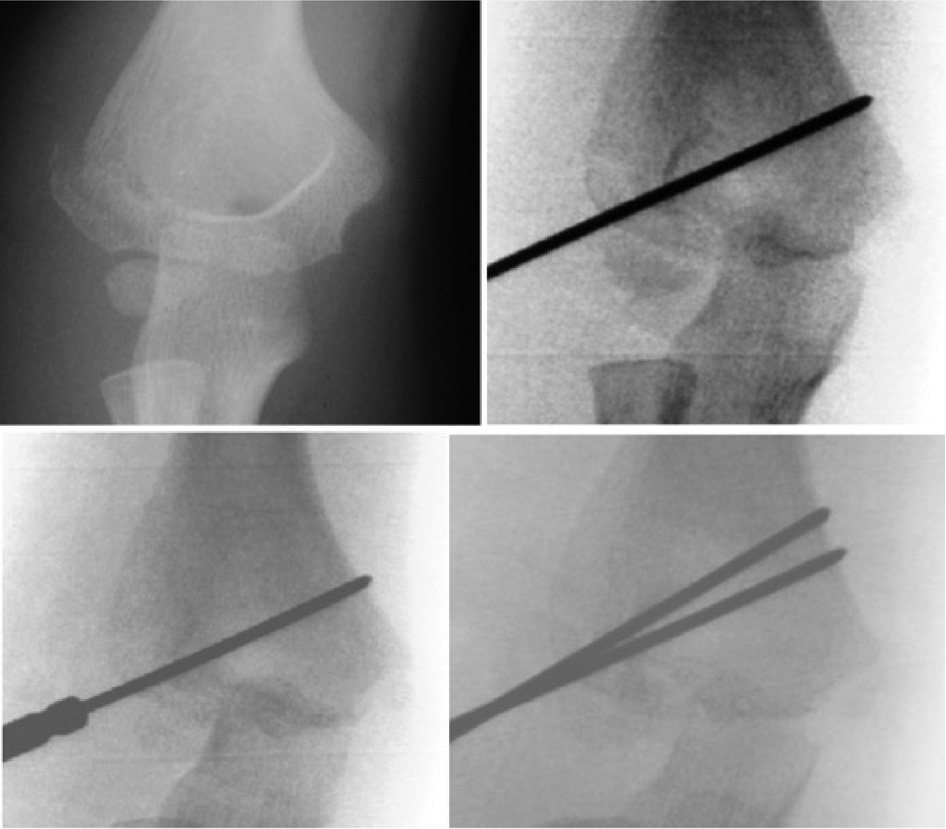

Lateral condyle humerus fracture (LCHF) is the second most common pediatric elbow injury. These injuries are intraarticular and are inherently unstable as the lateral condyle serves as the common extensor origin, which acts as a deforming force, resulting in nonunion of these injuries (Figure 8).33 As such, displaced LCHF are indicated for surgical fixation; percutaneous pinning is associated with shorter operating room times, lower risk of avascular necrosis, lower risk of damage to neurovascular structures, and less soft tissue trauma compared to open reduction and internal fixation.34,35

Figure 8. This child with a lateral condyle fracture underwent percutaneous pin fixation. After the first pin is placed, a cannulated drill bit is reversed and compresses the fracture while a second K-wire is placed divergently to hold the fracture compressed.

Fractures that are displaced greater than 2 mm or those with significant intraarticular involvement are indicated for surgical fixation. Once surgically identified, while preserving the posterior soft tissue attachments, the fragment can be reduced with the use of a K-wires as a joystick while visualizing the joint surface. Once reduced, at least two K-wires are placed bicortically: at least two lateral-to-medial column pins, perpendicular to the fracture line, may be used; alternatively, one may be placed transversely through the trochlea while the other is placed from the lateral column into the medial column36 (Figure 9).

Figure 9. Lateral condyle fractures have a tendency to displace due to pull of extensor mass. Tension band fixation with an absorbable suture can augment pin fixation.